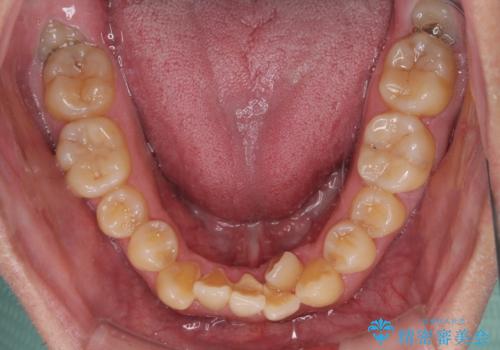

八重歯とクロスバイト 目立たないワイヤー装置で矯正治療

- 八重歯と前歯のクロスバイトを改善したいとのことで来院された患者様です。

デコボコの程度は強かったのですが、口元の突出感はなかったため、非抜歯矯正としました。

クロスバイトは、治療の過程で咬み合わせが大きく変化する期間があり、食事が取りにくくなってしまいます。

また、装置が対合歯と咬み合ってしまい、頻繁に脱落するなど、色々と面倒なことがあり、治療がスムーズに進まないことがあります。